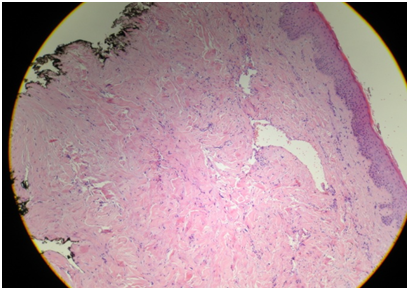

A female patient of 51 years of age consulted in March 2018 for asymptomatic, recurrent and autoinvolutive erythematous papules of 4mm in the left breast of 3months of evolution (Figures 1-3). Each lesion lasted a week. The patient was in oncological follow-up for left breast cancer of invasive ductal type diagnosed in 2016. She underwent quadrantectomy, axillary emptying and adjuvant chemotherapy with 4cycles of atracyclines (cyclophosphamide 1000mg and doxorubucine 100mg) and 12weeks of paclitaxel 80mg/m2/week. Additionally, they performed three-dimensional radiotherapy (RT) from July to October 2016. Then she continued on tamoxifen orally until today. With presumptive diagnoses of atypical vascular proliferation versus angiosarcoma versus cutaneous metastases, a punch biopsy was done of the most infiltrated lesion. The histology showed the presence in the reticular dermis of some irregular vascular channels that dissected the collagen, upholstered by flat endothelial cells or cuboids, without evidence of significant cytological atypia or mitosis. Focal erythrocyte extravasation coexisted (Figure 4). In the immunohisto chemistry, she had CD34 negative in the endothelium of the vascular channels, CK AE1 and AE3 and CK 7 negative for neoplastic cells and CD 68 positive in macrophage isolates (Figure 5). These changes were compatible with an atypical vascular lesion .

Figure 4 Irregular vascular channels dissecting the collagen, and flat endothelial cells without evidence of significant cytological atypia or mitosis.